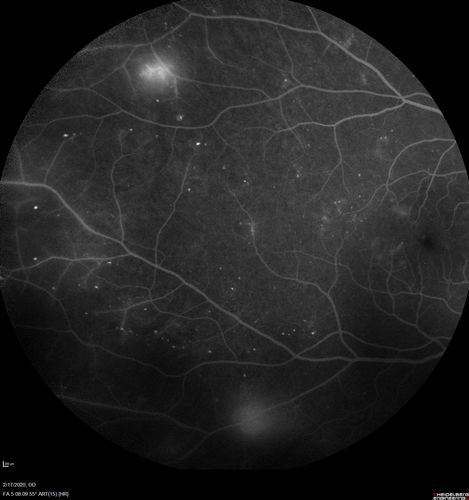

PDR and Vitreous Hemorrhage - High Risk Left Eye - Low Risk Right Eye

50 year old man with type I diabetes mellitus for 26 years. New Vitreous Hemorrhage in the left eye. Both eyes have NVE. Both also have foveal hypoplasia

Vitreous Hemorrhage and Proliferative Diabetic Retinopathy - Low risk right eye - High Risk Left Eye - Also Fovea Plana